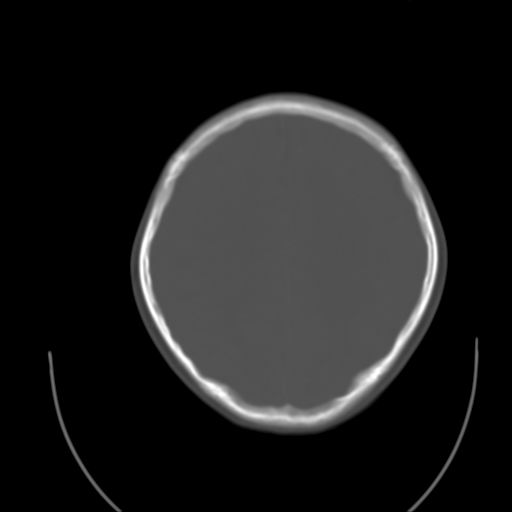

标题: PED1738:男 9岁左枕部包块。 [打印本页]

标题: PED1738:男 9岁左枕部包块。

猛一下想不起这个叫什么了,惭愧,请老师指导~~

左枕部头皮下血肿,有外伤史吗?

枕骨结节

左枕部皮下软组织密度增厚影---考虑-----左枕部头皮下血肿

考虑皮样囊肿可能性大

皮样囊肿可能性大.

皮样囊肿?皮下脂肪瘤?

软组织囊肿性病变可能性大

皮样囊肿?

考虑皮样囊肿。

考虑皮样囊肿可能性大。

皮样囊肿可能性大。